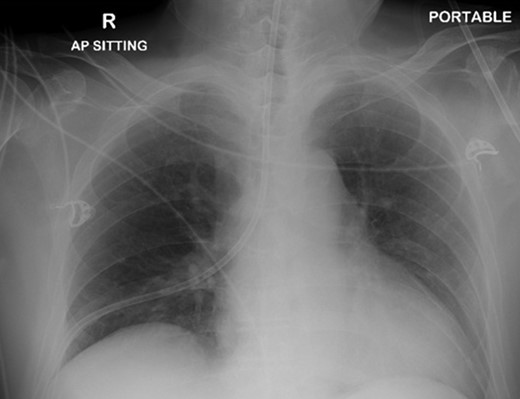

A 72-year-old male was admitted to a tertiary hospital following a cerebrovascular accident. His neurological deficits were global aphasia, dysphagia and right hemiplegia. He underwent a routine NGT change with a small bore NGT by an experienced nurse on Day 2 of admission. The nurse was unable to obtain any aspiration from the newly inserted NGT and a chest radiograph was done to confirm placement as per hospital protocol. This showed a malpositioned NGT, traversing the right main bronchus with the tip of tube in the right costophrenic sulcus (Fig. 1). She was alerted about the chest radiograph findings and removed the tube before reinserting another NGT. The subsequent aspiration from the NGT had a pH of 7, hence another chest radiograph was done which now demonstrated a right pneumothorax (Fig. 2). The pneumothorax was likely due to intrapulmonary placement of the earlier NGT.

Chest X-ray following removal of the nasogastric tube, with interval development of a right sided pneumothorax.